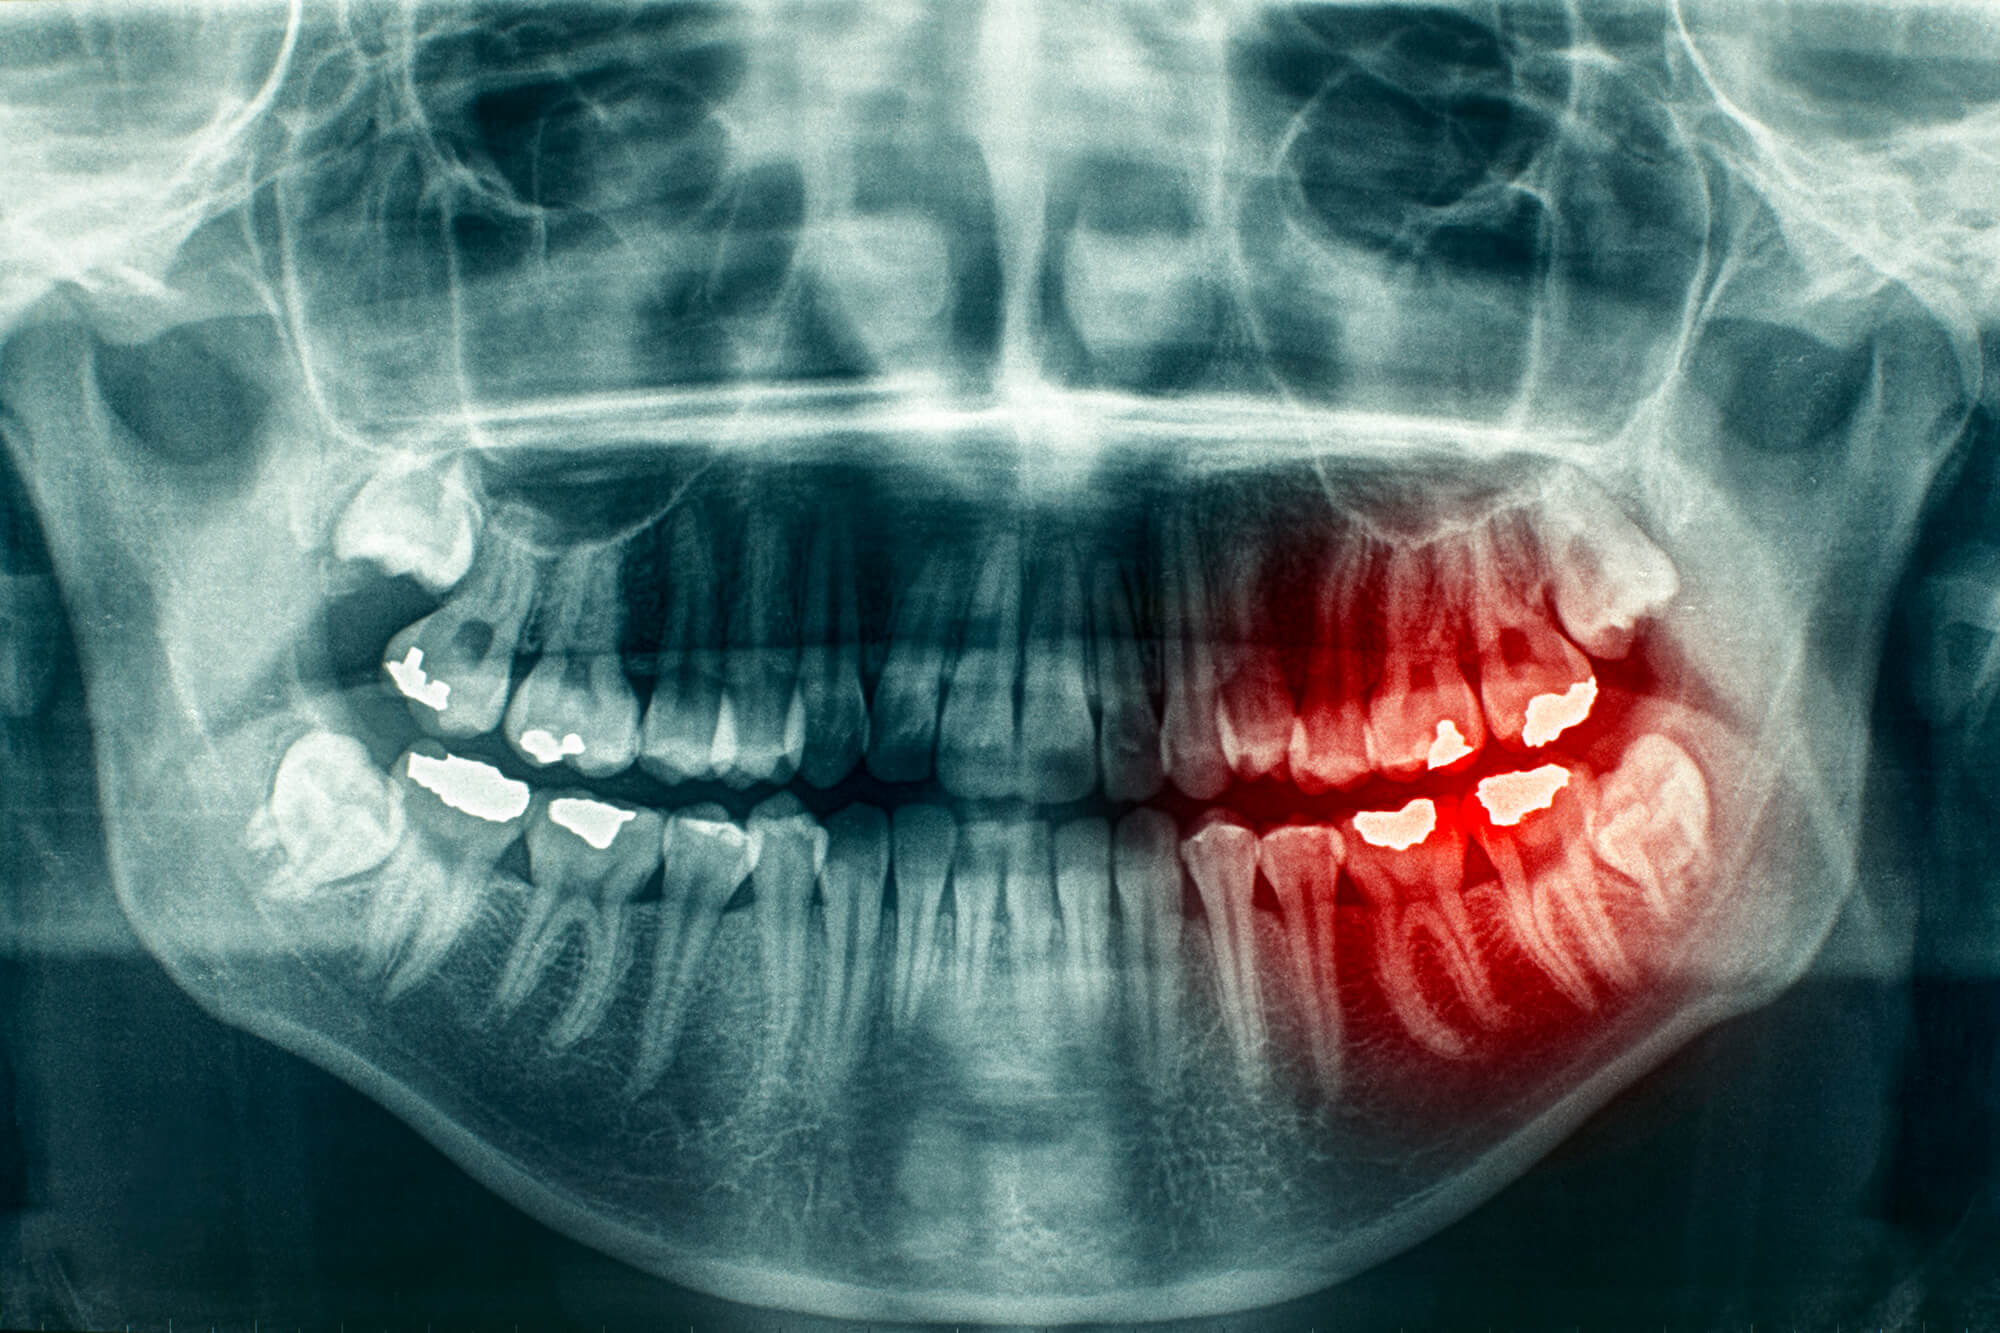

Is an X-Ray Necessary Before an Oral Surgery?

Most oral surgeries require an x-ray exam to guarantee that there are no obstacles along the way. Complications may develop if oral surgeons perform a procedure without knowing what’s going on inside. It is necessary to guide oral surgeons in looking inside your teeth, mouth, and jaw. With today’s advanced technology, x-ray machines are designed to emit low radiation to ensure safety and reduce side effects.